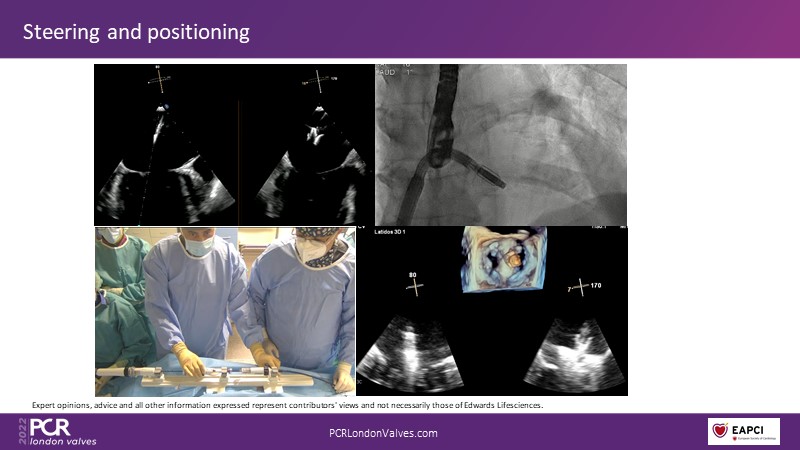

The new PASCAL Precision system unleashes the full potential of mitral transcatheter edge-to-edge repair

Join this panel of experienced physicians to learn more about the novel PASCAL Precision system and to discuss implant selection and clinical data. Finally, participate in a recorded case demonstrating the use of the PASCAL Precision system for the treatment of mitral regurgitation.